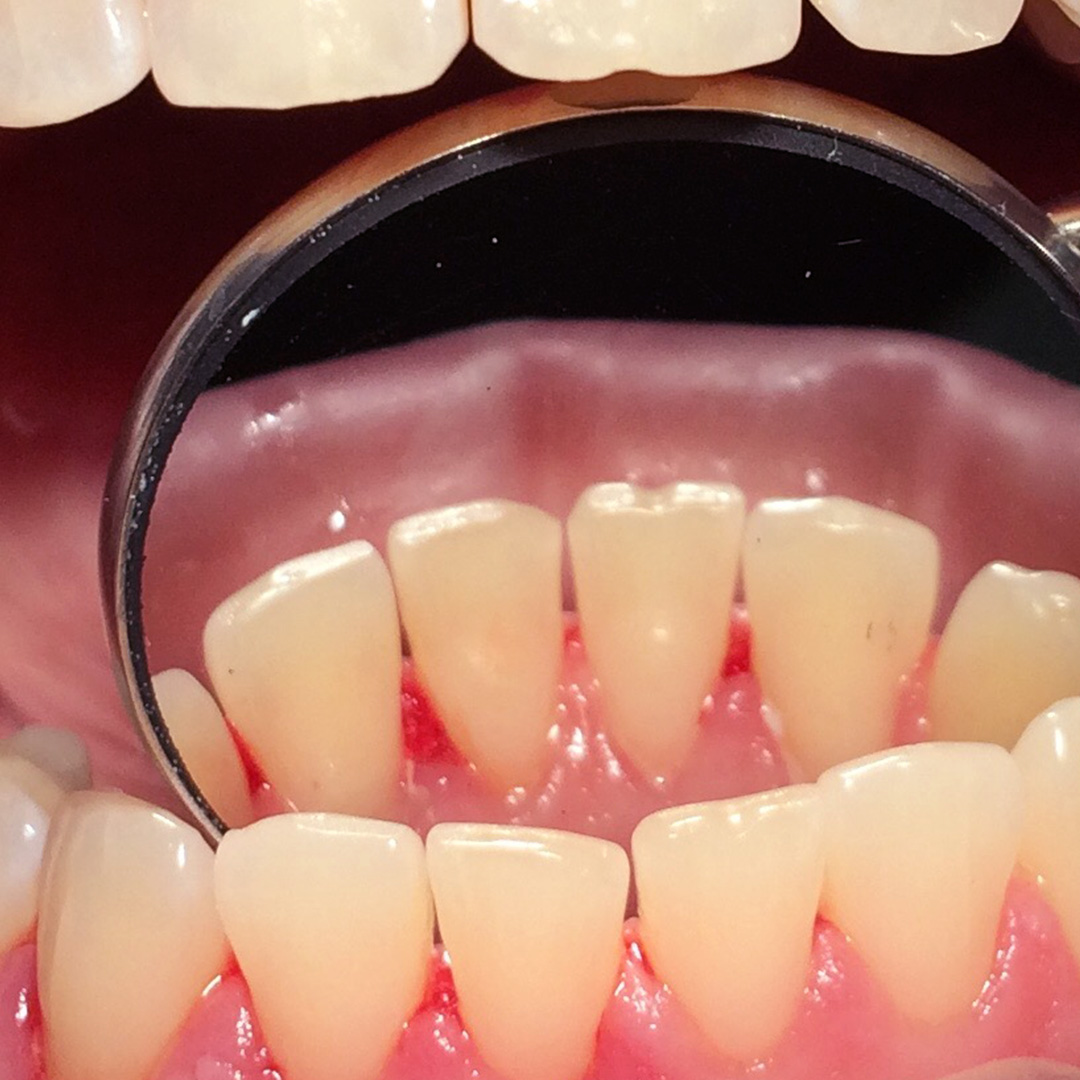

До и после лечения

Врач выполнил следующие действия:

- профессиональная гигиена с помощью ультразвукового аппарата;

- чистка зубов аппаратом air-flow;

- полировка щёточками и пастами;

- даны рекомендации по ежедневной личной гигиене полости рта.